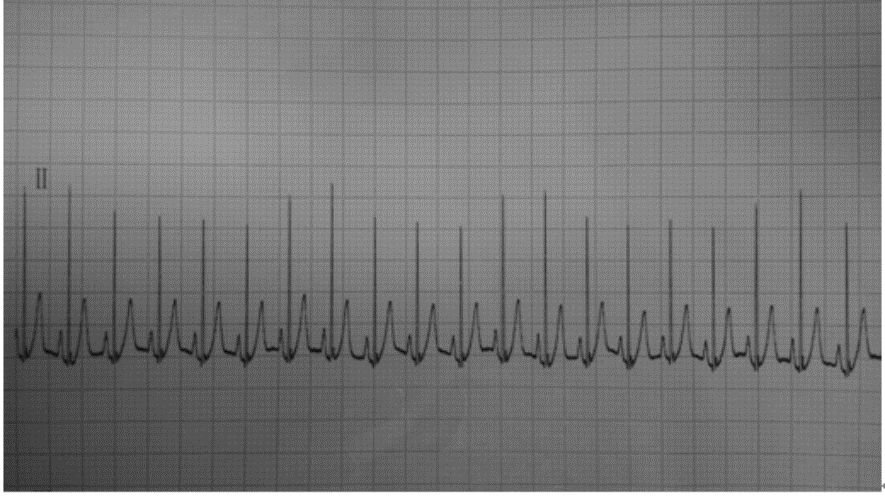

图 1显示ΔRⅡ随着呼吸周期显著的周期性变化,观察研究发现呼吸周期性ΔRⅡ与SVV呈正相关性(r=0.807,P<0.01见图 2),而呼吸周期性ΔR Ⅲ、ΔR AVF与SVV的相关性分别为(r= 0.453,P=0.016,r=0.642 ,P<0.01,分别见图 3、4);

| 图 1 机械通气所致的呼吸周期性R波幅度变异 |